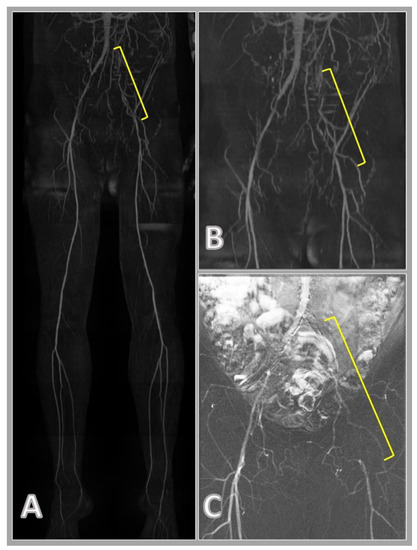

洋書 Cardiovascular Magnetic Resonance, 2e Quiescent-Interval Single-Shot Magnetic Resonanceの詳細情報

Quiescent-Interval Single-Shot Magnetic Resonance。。。